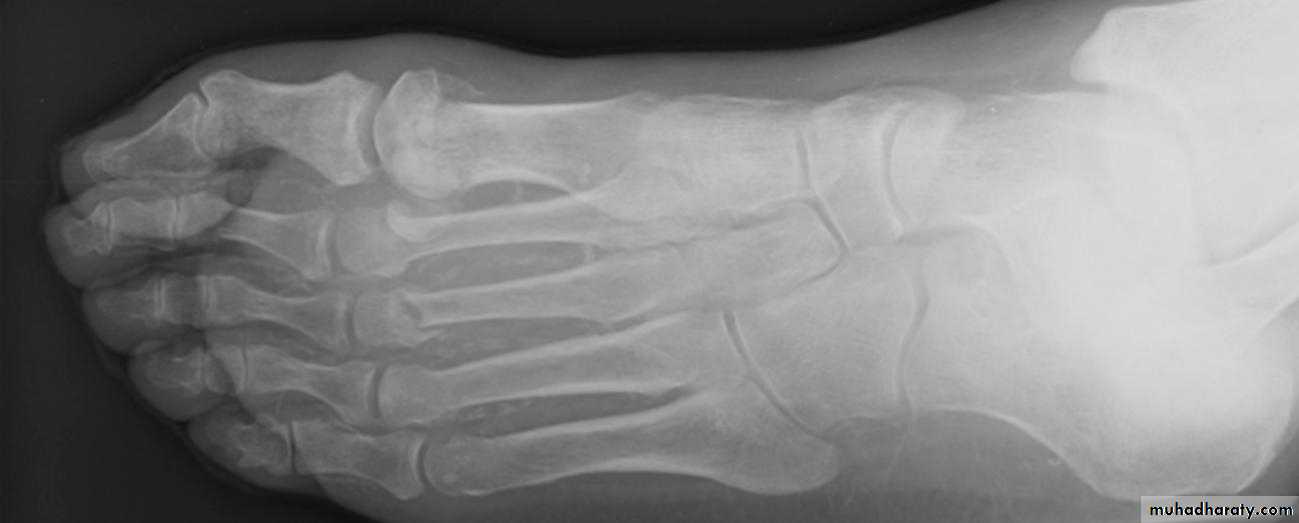

A plain radiograph

of the foot showed fractures through the necks of the first three metatarsals (fig 2⇓). We offloaded the foot in a total contact cast and advised the patient to limit weight bearing.Magnetic resonance imaging (MRI) subsequently confirmed neuroarthropathic changes of acute Charcot (fig 3⇓).

Standard radiographs are an important first line investigation.The finding of fractures or bony misalignment in the absence of obvious trauma is highly suggestive of Charcot foot (fig 2).

Plain radiograph of the foot showing fractures through the necks of the first three metatarsals